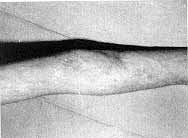

Fig.

5a - Retractile scar in the elbow. |

5b - Removal of scar. Tendons and vessels exposed. Correction with epigastric

flap. |

5c - Result 6 months later. |